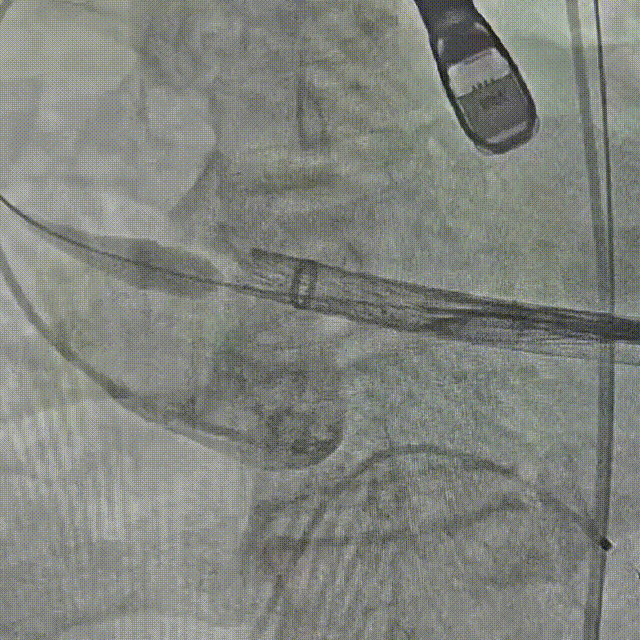

辅入路猪尾根部造影(右窦居中)

瓣膜初始定位

瓣膜开花后造影确认位置

起搏下释放瓣膜至全展开

全展开后造影评估

瓣膜打平造影评估

瓣膜位置可,形态可

脱钩后造影,瓣膜无位移,形态可

弓部剪影,无瓣周漏,升主无损伤